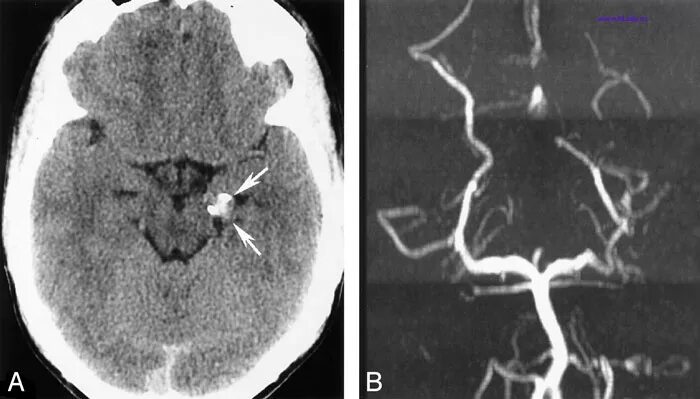

Аневризма головного мозга на кт